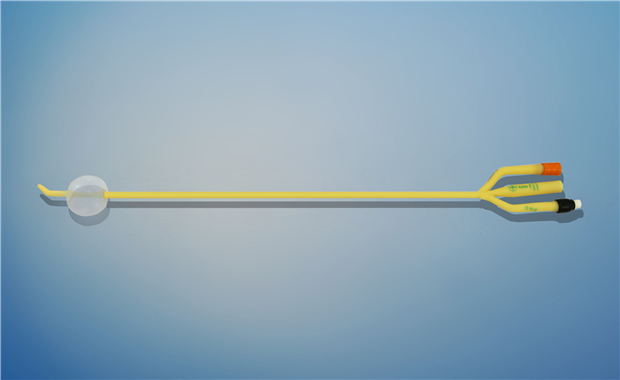

【產品名稱】一次性使用無菌導尿管(取樣型使用) 【型號】雙腔彎頭取樣型 【規格】:12FR-18FR 【主要結構����、性能】由膠乳為主要原材料制成,可配卡片���。

型號:雙腔氣囊彎頭型規格:雙腔氣囊彎頭型:12Fr(5-10mL)���、14Fr(5-10mL)����、16Fr(5-10mL)���、16Fr(30mL)�、18Fr(30mL)����;結構及組成/主要組成成分:產品由導尿管、水潤滑包(選配)組成。雙腔由球囊腔充起錐形接口�、排液腔錐形接口、閥門����、管身、球囊�、排液孔組成(尖端有普通尖頭和彎頭區...